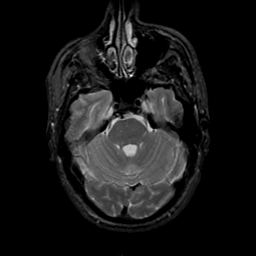

MR Study #18, July 21, 1991 -- Slice #14